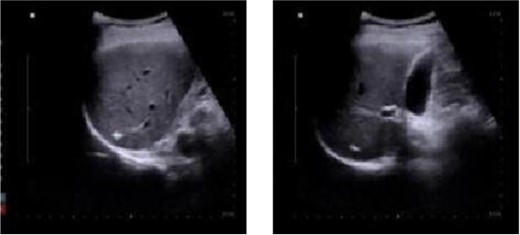

A 50-year-old male patient is diagnosed with mixed hemorrhoid. He reported no prior medical history of hypertension; diabetes; cardiovascular, pulmonary, hematological disorders. The patient’s symptom was the prolapse of the anal mass after each stool and lasted for >2 years. Proctoscopy revealed the presence of two large external hemorrhoids with three internal hemorrhoids in the 3, 7, and 11 o’clock position. The patient underwent hemorrhoidectomy under combined lumbar epidural anesthesia. The surgery went smoothly. Unfortunately, on the second day post-surgery, the patient developed sudden chills and fever, with a body temperature of 39.9°C. Urgent investigations revealed the following: routine blood analysis showed white blood cells at 13.28 × 10^9/L, platelets at 307 × 10^9/L, lymphocyte percentage at 8.1%, and neutrophil percentage at 89.2%. The patient received intramuscular lyserpyrine injection (0.9 g), fluid rehydration, and physical cooling. Consequently, the patient’s body temperature decreased to 37°C. On the third morning post-surgery, the body temperature rose to 38.5°C. Further routine blood analysis revealed the following critical values: white blood cell count, 35.3 × 10^9/L, lymphocytes, 1.9%; and neutrophils, 95.2%. Examination of the wound tissue revealed no purulent exudate. The patient reported upper abdominal pain accompanied by nausea and reduced appetite. A prompt abdominal color ultrasound examination indicated a cystic solid echo near the right lobe of the liver, adjacent to the diaphragmatic apex, measuring ~29 × 26 mm, with indistinct borders. The diagnostic impression from the abdominal color Doppler ultrasound suggested a hepatic abscess (Fig. 1).

Abdominal color ultrasound findings on the third day after surgery.

The patient received anti-infective therapy comprising imipenem and cilastatin sodium along with a high-calorie digestible diet. By the sixth day post-surgery, the patient exhibited normothermia, improved appetite, and alleviation of abdominal discomfort. Subsequent routine blood analysis revealed a white blood cell count of 11.79 × 10^9/L, lymphocyte percentage of 21.3%, and neutrophil percentage of 70.7%. Re-evaluation using abdominal color ultrasound on postoperative Day 12 revealed that the extent of the abscess in the right hepatic lobe was reduced to 24 mm × 19 mm (Fig. 2).

Abdominal color ultrasound findings on the 12th day after surgery.